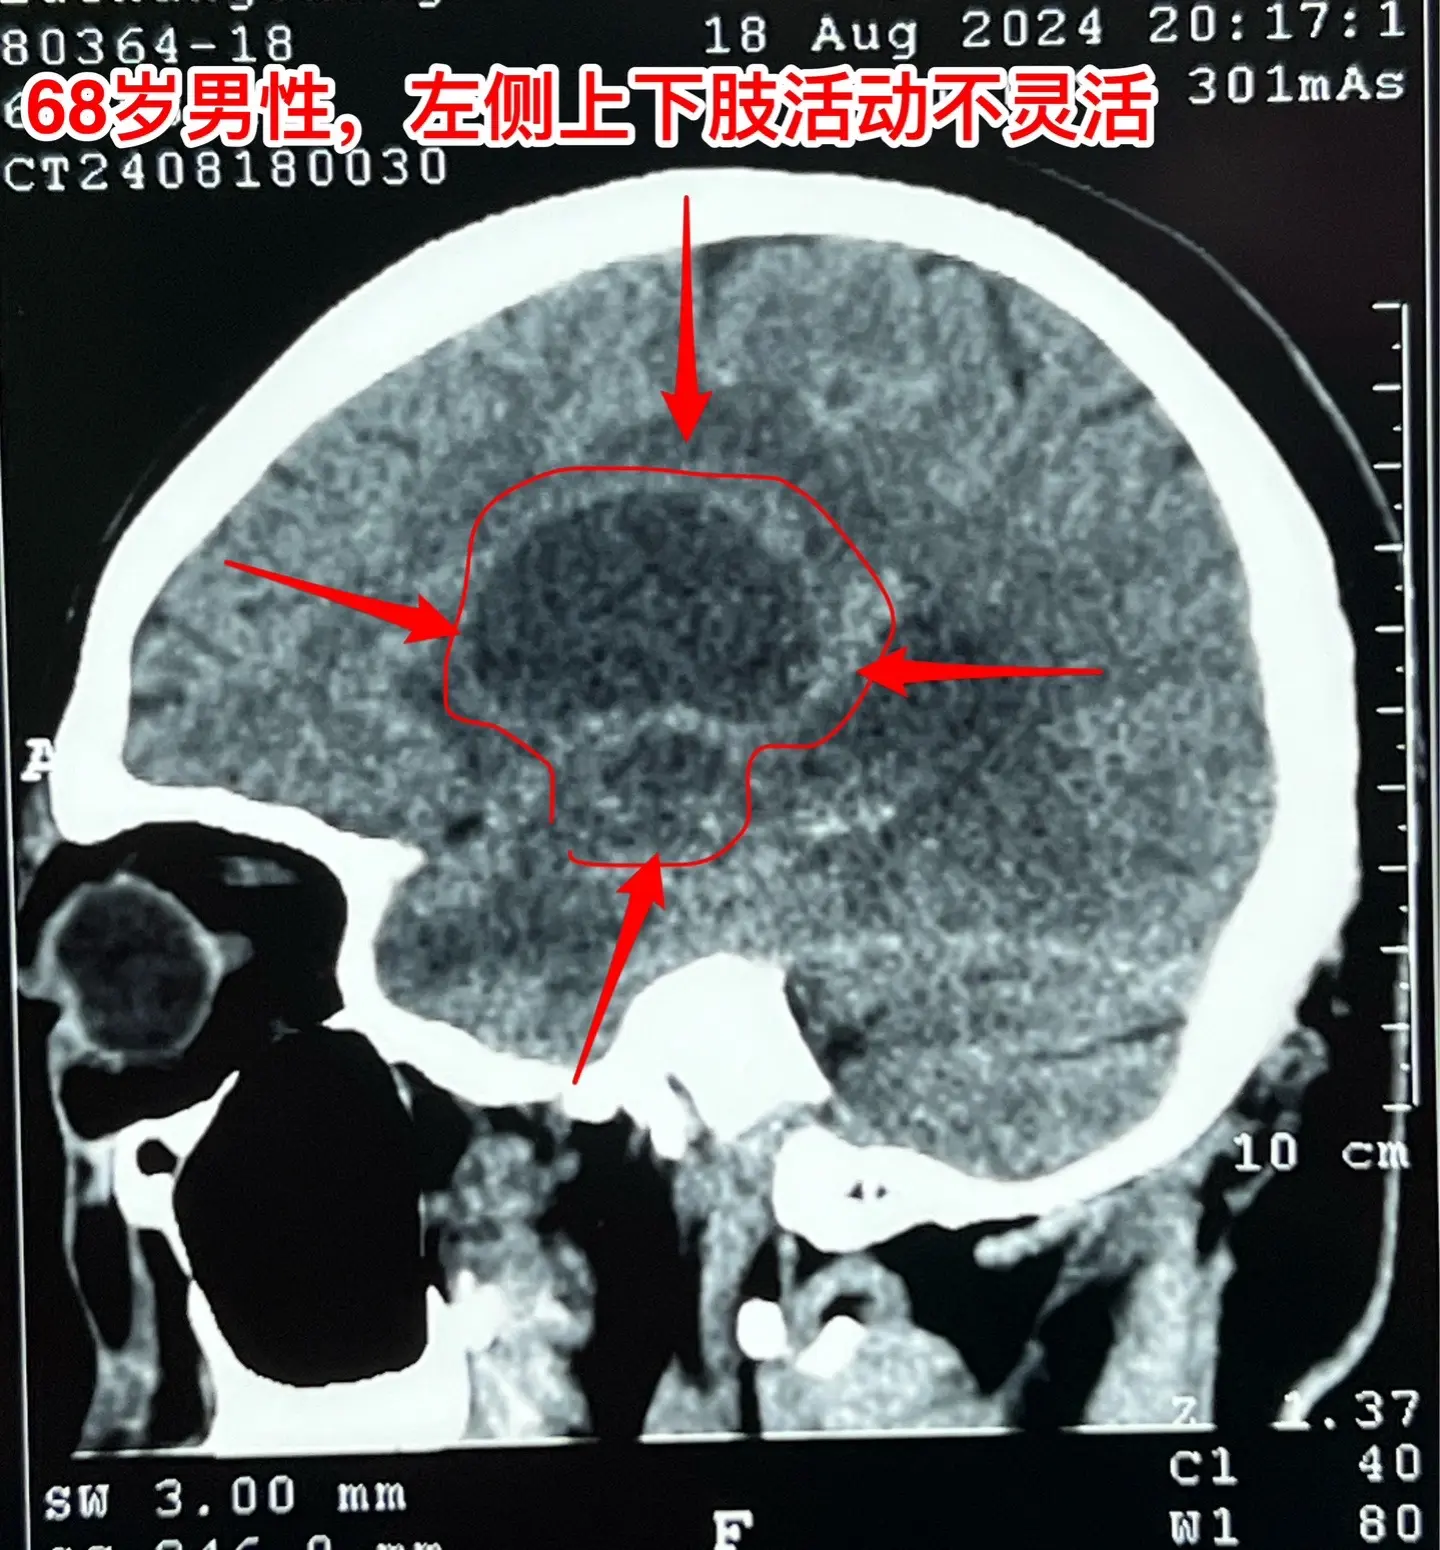

老人擀饺子皮的质量下降了,原因是什么?68岁的唐山市老人,擅长擀饺子皮、包饺子,平时擀出的饺子皮中央稍厚、四周均匀薄。然而近期他擀出的饺子皮形态不规整,厚薄一致,与平时的水准大相径庭,是什么原因呢?而且家人发现他穿鞋系鞋带动作又慢又笨拙!跟平时完全不一样。 病人的女儿在北京当医生。 到医院去检查脑部磁共振就发现脑部长了一个瘤。这个瘤位于左侧颞叶-基底节区,压迫内囊区域,虽然没有造成明显的偏瘫症状,但是也造成了左侧上下肢活动不灵活。 8.16到我这里来住院,8.23作了手术,术中的快速冰冻病理提示高级别神经上皮肿瘤,即胶质瘤的一种。 手术后老人没有出现明显的偏瘫症状。 这样的肿瘤单纯作手术是不够的,还需要作放疗、化疗。